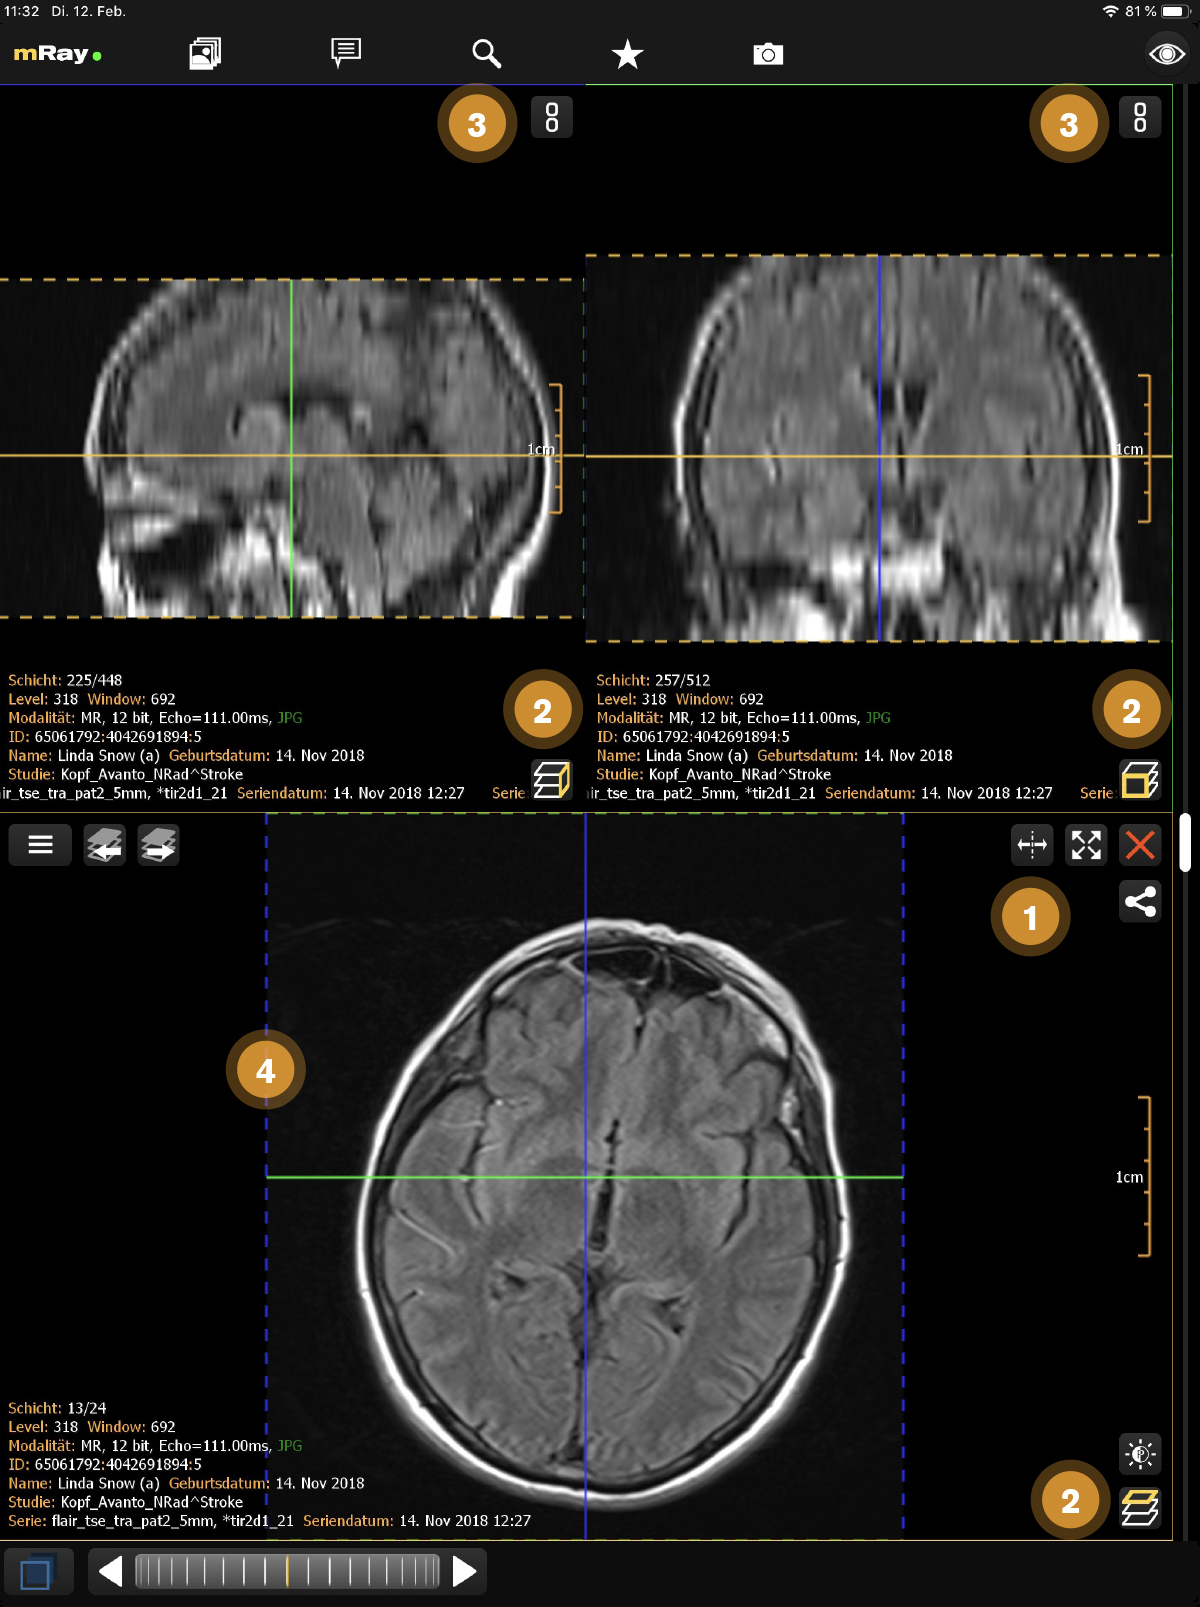

10.4. MPR-Ansichten

Die MPR-Bildlaufleiste erlaubt es Ihnen, mehrere Ansichten gleichzeitig zu öffnen (MPR-Ansichten). Der folgende Screenshot zeigt die MPR-Bildlaufleiste:

Der Screenshot zeigt die MPR-Bildlaufleiste eines MRTs von einem Fuß, die lokal berechnete Rekonstruktion (MPRs) und Informationen zum angezeigten Datensatz.

-

Der Split-Button

erlaubt es dem Nutzer weitere Fenster hinzuzufügen.

Die maximale Anzahl von Fenstern beträgt 2 bei Smartphones und 4 bei Tablets.

Vorübergehende Anzeige der Ansicht im Vollbildmodus und Rückkehr zum vorherigen Zustand mit den Maximieren

erlaubt es dem Nutzer weitere Fenster hinzuzufügen.

Die maximale Anzahl von Fenstern beträgt 2 bei Smartphones und 4 bei Tablets.

Vorübergehende Anzeige der Ansicht im Vollbildmodus und Rückkehr zum vorherigen Zustand mit den Maximieren  und Minimieren

und Minimieren  -Buttons.

-Buttons. -

Zeigt die aktuelle Ausrichtung der Ansicht in Bezug auf den originalen Datensatz. Button

, um die Ansichten zu wechseln.

, um die Ansichten zu wechseln. -

Der Verketten-Button

synchronisiert die Fenster.

synchronisiert die Fenster. -

Zeigt die Referenzlinien zu den jeweils anderen Fenstern.

Sie können die Perspektive mit dem "MPR-Perspektive"-Button (Punkt 2) verändern. Diese Funktion erlaubt es, zwischen Axial, Sagittal und Coronal zu wechseln. Der Button in der rechten unteren Ecke (Punkt 1) ermöglicht das Öffnen oder Schließen von weiteren Ansichten. Falls mehr als eine Ansicht geöffnet ist, erscheint ein Button um diese zu synchronisieren (siehe Synchronisierte Ansichten). Um mit der Ansicht interagieren zu können, müssen Sie entsprechende Ansicht zunächst auswählen. Dazu müssen Sie die Ansicht nur antippen. Die ausgewählte Ansicht wird dann hervorgehoben.

10.4.3. Synchronisierte Ansichten

Falls mehrere Ansichten geöffnet wurden, erscheint ein Button mit einem Kettensymbol ![]() mithilfe dessen die Ansichten bezüglich des Schichtenblätterns miteinander synchronisiert werden können (siehe Synchronisierte Ansichten).

mithilfe dessen die Ansichten bezüglich des Schichtenblätterns miteinander synchronisiert werden können (siehe Synchronisierte Ansichten).

Diese Funktionalität erlaubt es Interaktionen auf der aktiven Ansicht mit anderen Ansichten zu synchronisieren. Folgende Interaktionen werden synchronisiert: